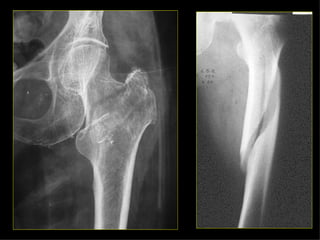

Tipos Fractura patológica.  Causa local (carcinoma metastásico), suelen ocurrir a nivel de los cuerpos vertebrales, 1/3 proximal del fémur y ½ proximal del húmero.  Causa generalizada (osteoporosis senil), con afectación fundamental en los cuerpos vertebrales dorsales y lumbares, así como el cuello del fémur. Enfermedad local. Tumores benignos. Encondroma. Tumores  malignos. Ca. Metastásico. Infección. Osteomielitis. Otros. Quiste simple. Displasia fibrosa. Granuloma eosinófilo. Lesiones difusas. Congénitas. Ostg. Imp. Adquiridas. Varios.